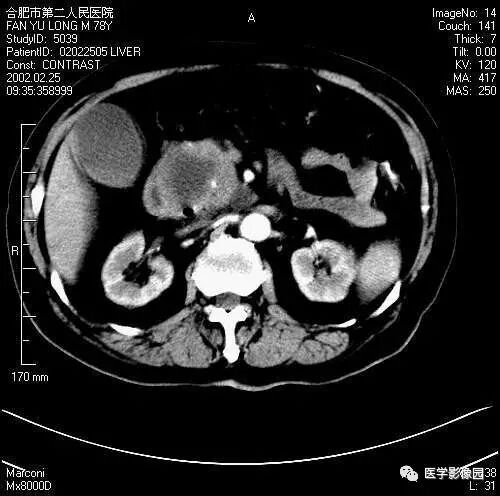

图6-4-12胰腺癌

增强扫描胰腺钩突失去正常平直的三角形,

呈不规则分叶状